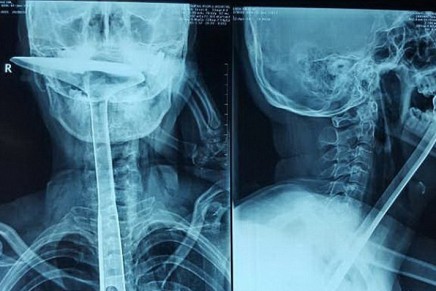

Le dio un ataque de alergia y se le inflamaron las cuerdas vocales, se intentó aliviar con este utensilio y finalmente tuvo que ser operada. ¡Vaya susto! Escucha la historia en La Otra Realidad con Patricia Imaz y como se las gastan en la selectividad en China.